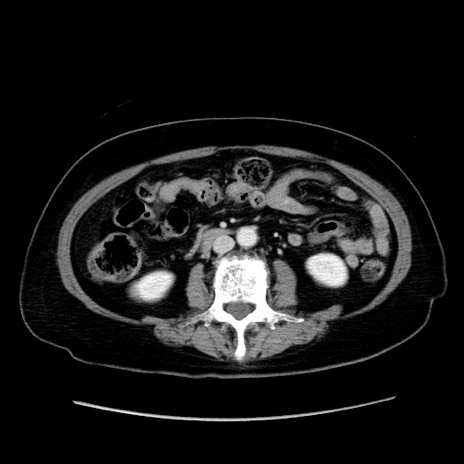

症例19(横断像)

【症例】80歳代女性

【主訴】下腹部痛

【現病歴】約8時間前より下腹部痛の出現あり、救急外来受診。

【既往歴】両側付属器切除

【身体所見】意識清明、下腹部正中に手術痕あり、その部位に一致して圧痛と反跳痛あり。腸蠕動音は亢進。

【データ】WBC 9300、CRP 0.15